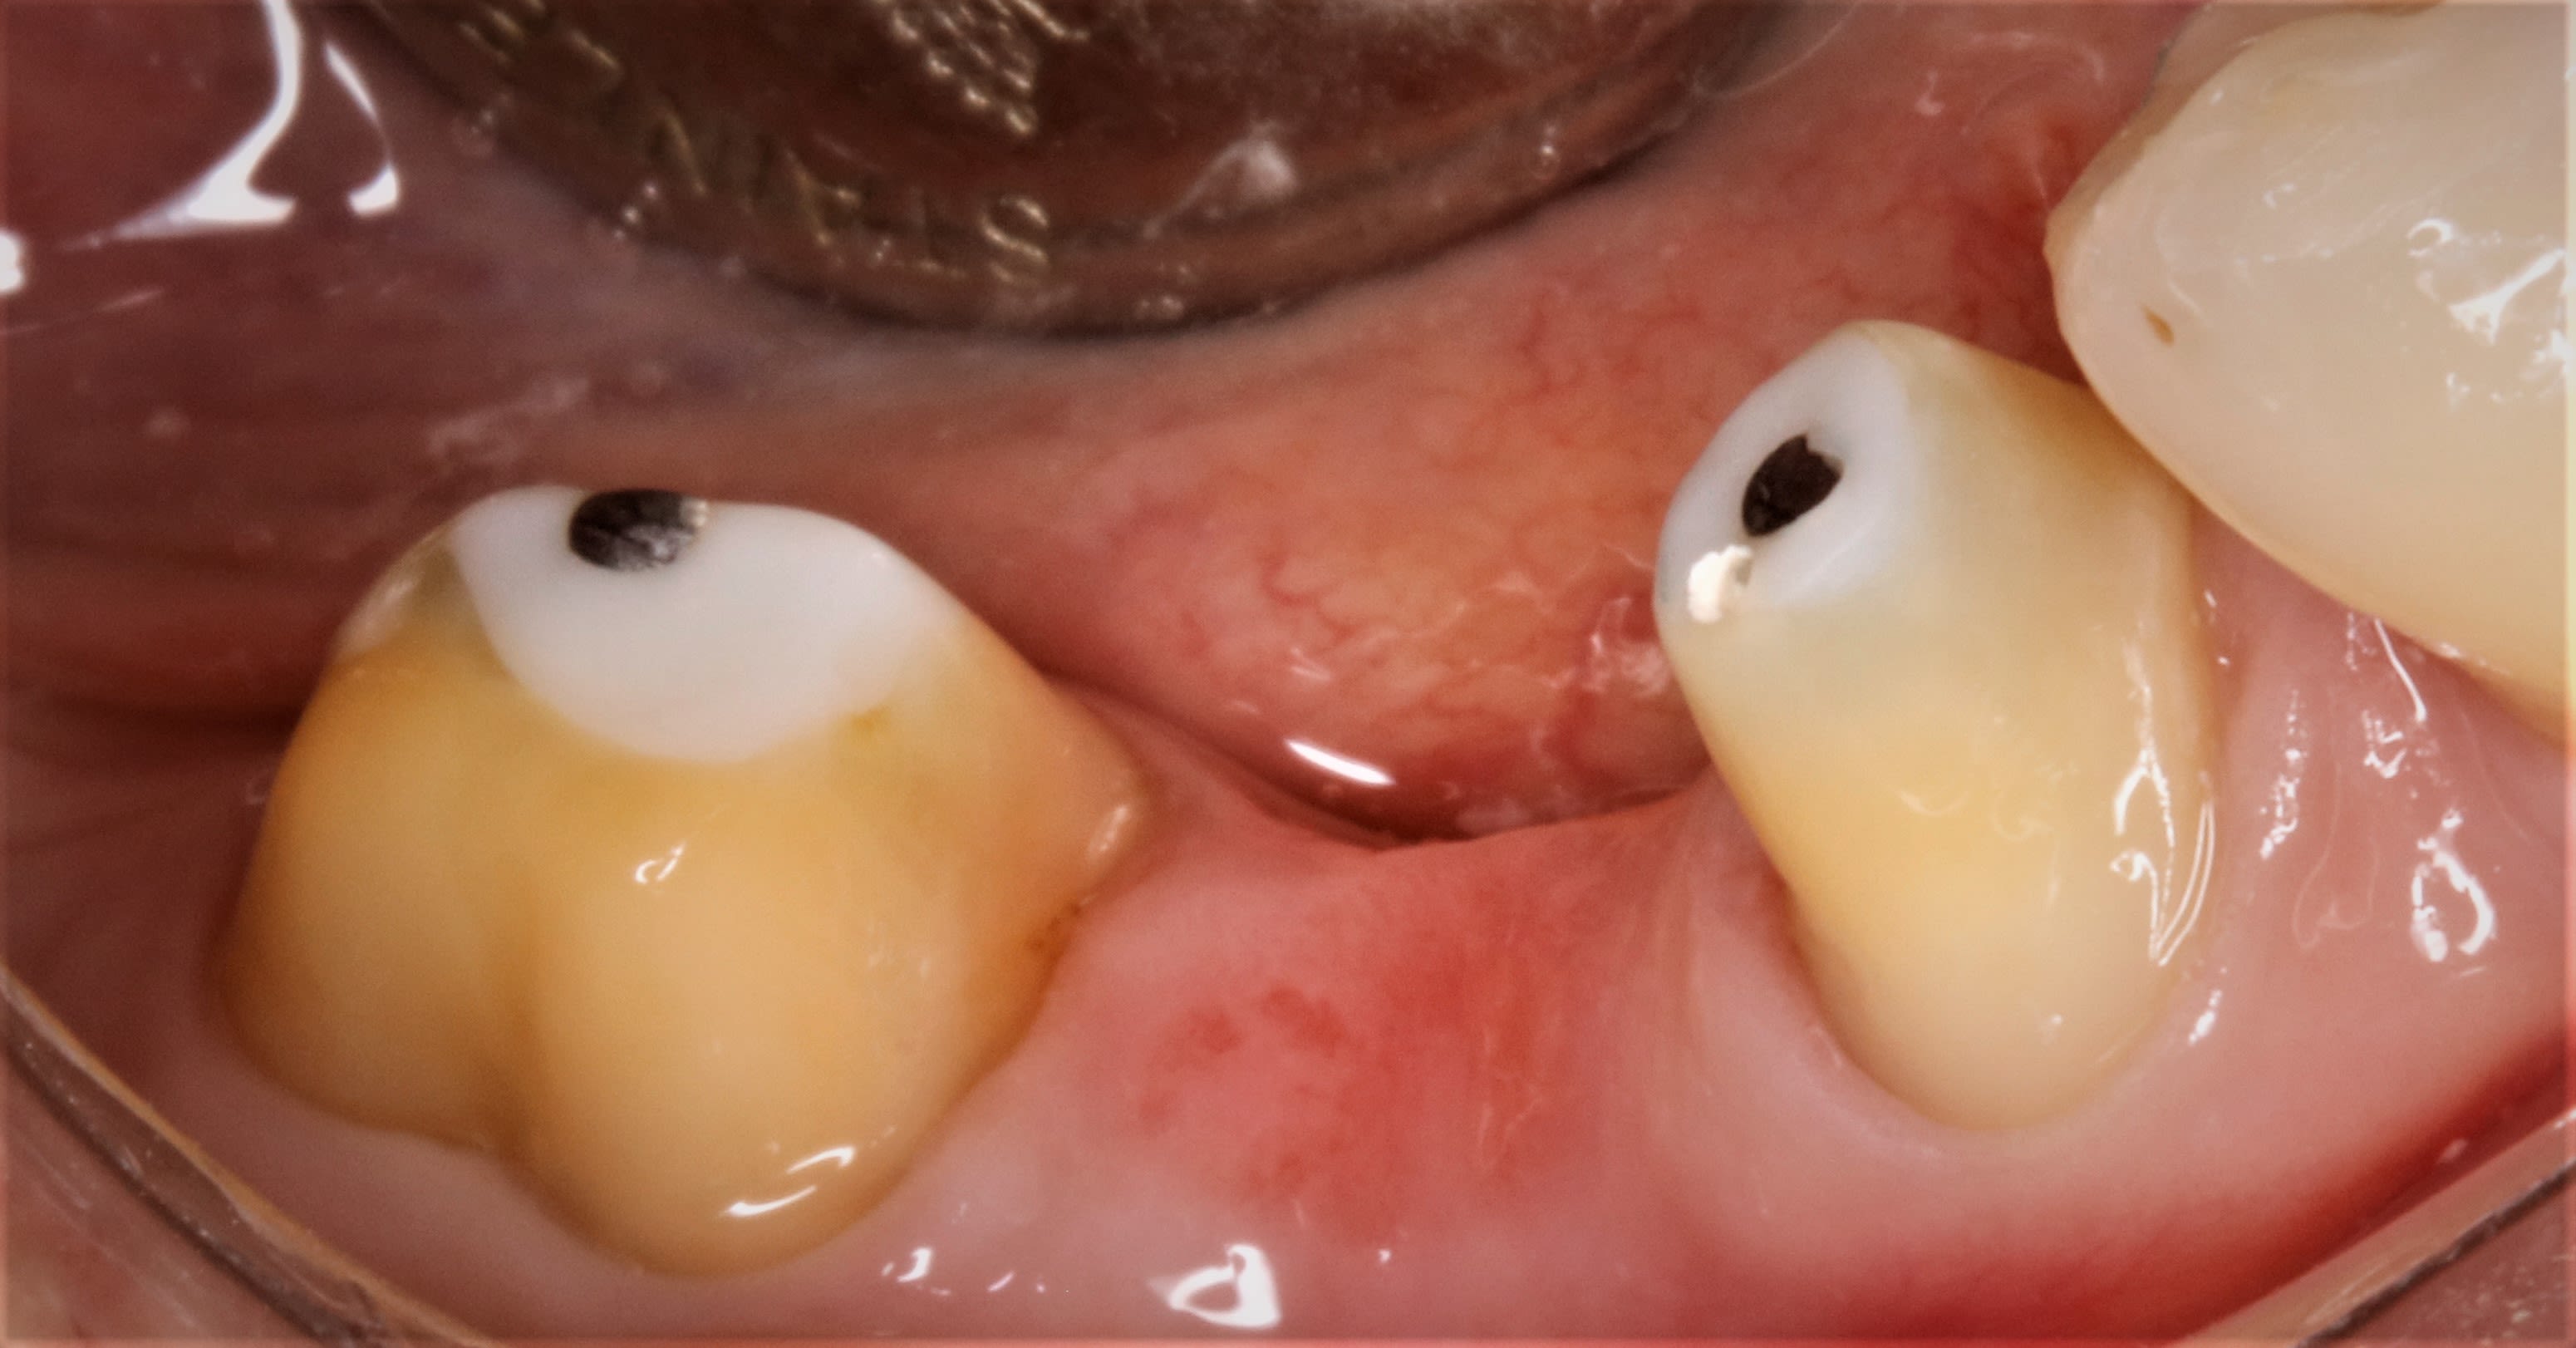

Provisoire en automoulage réalisée en bouche.

Img 20191217 120230 n6b04c - Eugenol